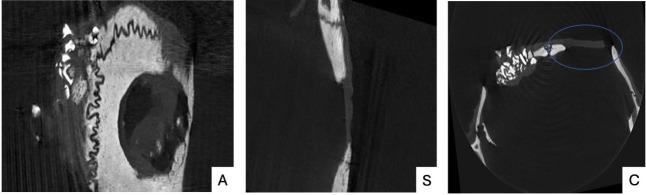

Melatonin (MLT) is a hormone that can stimulate bone formation and inhibit bone resorption, among other functions. Aim: To evaluate the effect on new bone formation of MLT applied locally to critical defects created in the calvaria of rats, compared to the effect of Bio-Oss® xenogeneic bone substitute (BO), by analyzing histomorphometry, microtomography and gene expression. Materials and Method: Two critical defects (5.0 mm in diameter) were created in the calvaria of 36 adults male Wistar rats. The rats were divided randomly into two groups: a test group, in which one of the defects was filled with MLT, and the other with MLT with Bio-Oss® (MLTBO), and a control group, in which one of the defects was filled only with the clot (C), and the other with BO. The rats were euthanized 30 days after surgery. Samples of the calvaria containing the critical defects were collected for analysis by histomorphometry, microtomography, and the expression of the genes for type I collagen (COL-I), osteopontin (OPN) and bone morphogenetic protein 2 (BMP-2). Results: A qualitative improvement was observed in bone healing when MLT was used, though there was no statistical difference in the quantification of newly formed bone (p>0.05). Micro-CT showed that bone volume was significantly smaller in absence of BO (p=0.006). Bone trabeculae thickness (p=0.590) and number (p=0.150) were not significantly affected by MLT. Regarding the expression of the genes COL-I, OPN and BMP-2, no significant differences were observed between the MLT, BO and MLTBO groups. Conclusion: Topical application of MLT resulted in a qualitative improvement in bone healing, although it did not affect bone formation quantitatively. In the absence of BO, less bone volume and less bone trabecular thickness were observed.